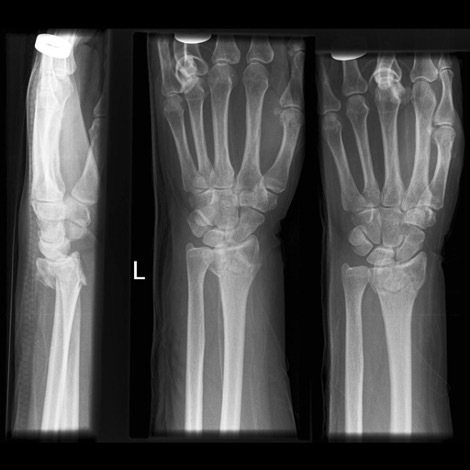

Colles’ fracture

**Colles - ‘dinner fork type deformity’** Features of the injury 1. Transverse fracture of the radius 2. 1 inch proximal to the radio-carpal joint 3. Dorsal displacement and angulation of the distal radius

Colles vs Smith fracture

Colles fracture ## Footnote Typically FOOSH forwards Extra-articular radial # with dorsal (posterior / back of hand) angulation and displacement